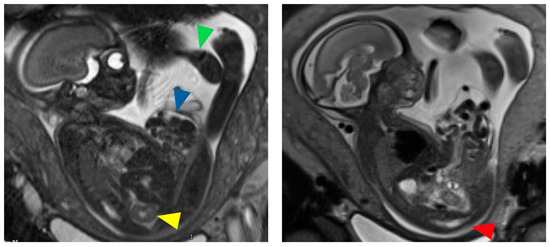

- Weiss, D.A.; Oliver, E.R.; Borer, J.G.; Kryger, J.V.; Roth, E.B.; Groth, T.W.; Shukla, A.R.; Mitchell, M.E.; Canning, D.A.; Victoria, T. Key Anatomic Findings on Fetal Ultrasound and MRI in the Prenatal Diagnosis of Bladder and Cloacal Exstrophy. J. Pediatr. Urol. 2020, 16, 665–671. [Google Scholar] [CrossRef] [PubMed]

- Morrill, C.C.; Haffar, A.; Crigger, C.; Black, M.; Jelin, A.; Nasr, I.; Gearhart, J.P. A Single-Institutional Experience With Prenatal Diagnosis of Cloacal Exstrophy: Room for Improvement. J. Pediatr. Surg. 2023, 58, 1949–1953. [Google Scholar] [CrossRef] [PubMed]